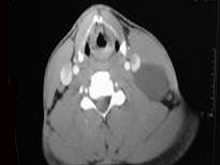

| 十产岁患者,女性,因颈前正中包块3年入院,查体:颈前胸锁乳突肌前缘上1/3外可触及一圆形包块,囊性,无压痛,不随吞咽上下活动。 |

6.CT检查结果见下图,本患者应考虑为 ( )![]() ![]() ![]() ![]() |

| 正确答案:6.C;7.E |